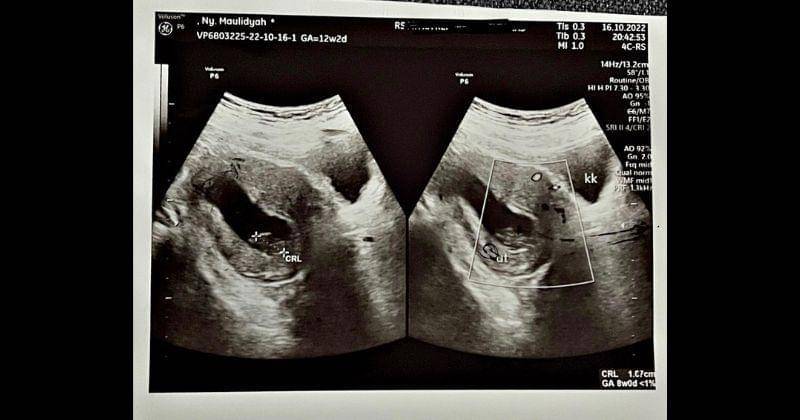

5. Usia janin Via harusnya 12 minggu, tetapi menurut dokter masih stuck di usia 8 minggu

Dalam keterangan Instagram itu, Via menceritakan kepedihan dirinya yang mengalami janin tidak berkembang di kehamilan pertama yang begitu ia nantinya. Ia menyebut HPHT (Hari Pertama Haid Terakhir) pada 22 Juli 2022 kemarin, dengan hasil tes di tanggal 16 Agustus 2022 memiliki 1 garis tebal dan 1 garis samar.

"Menurut hitungan dokter, seharusnya usia kamu 12 minggu nak. Tetapi hasil USG menyatakan usia kamu masih 8 minggu (sama dengan hasil USG 1 Oktober 2022 kemarin)," kata Via.

Dari sana, Via mendapatkan hasil kalau jabang bayi kesayangannya itu sudah tidak berkembang selama satu bulan. Via pun dilanda kebingungan besar dengan hal ini. Ia memutuskan untuk menunggu lagi dan berharap janinnya bisa berkembang normal.

"Kata dokter, kamu sudah nggak berkembang selama 1 bulan. Ami bingung nak, demi Allah bingung. Melihat kondisi yang sekarang, apakah mungkin dengan menunggu lagi, masih ada harapan untuk kamu berkembang dan bisa benar-benar Ami miliki," jelasnya.